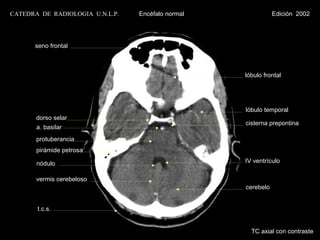

seno frontal

lóbulo frontal

lóbulo temporal

dorso selar

cisterna prepontina

a. basilar

protuberancia

pirámide petrosa

nódulo                                      IV ventrículo

vermis cerebeloso

cerebelo

t.c.s.

TC axial con contraste